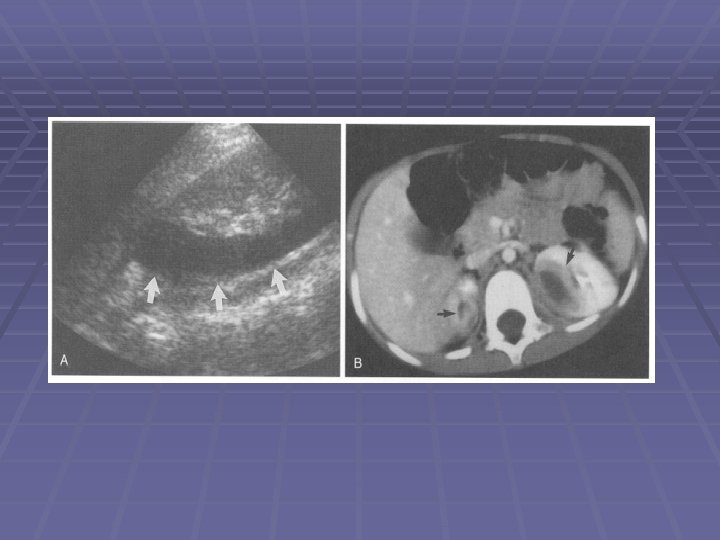

IMAGING STUDIES Detection, localization, characterization, and guidance in aspiration and for follow-up. § Ultrasonography: Quickest and least expensive The usual initial examination Should be performed in individuals presumed to have acute pyelonephritis that gives rise to atypical findings or is unresponsive to antibiotic treatment May not permit distinction between abscess, phlegmon (nephronia), and uncomplicated pyelonephritis. § Doppler ultrasonography: absence of blood flow in a liquefied abscess § Contrast-enhanced (MRI) and (CT): devascularized nonexcreting areas replacing normal renal parenchyma CT appears to be the diagnostic procedure of choice for renal abscesses § Renal cortical scintigraphy, gallium-67 citrate scanning, and technetium 99—labeled leukocyte scanning : reveal focal masses in the kidney,

§ Patients recovering from a renal abscess should undergo serial sessions of renal ultrasonography to document progress. § Resolution of the ultrasonographic abnormality lags behind clinical and laboratory signs of improvement. § Renal “masses” often take months to resolve. § In many instances, it will be difficult to definitively distinguish a renal abscess from a renal tumor. …. . radiologic-guided drainage with analysis of fluid can be helpful in establishing the diagnosis.

§ 1: Pediatr Infect Dis J. 2004 Jan; 23(1): 11 -4. Links Effective ultrasonographic predictor for the diagnosis of acute lobar nephronia. BACKGROUND: Correct identification of acute lobar nephronia (ALN) is necessary to prevent progression to renal abscess. The goal of this retrospective study was to determine whether the sonographic finding of severe nephromegaly (i. e. renal length greater than mean + 3 sd) is a preselection criterion for computed tomographic (CT) scanning in diagnosing pediatric ALN among children with an acute upper urinary tract infection. DESIGN/METHODS: ……All patients with urinary tract infection were evaluated with ultrasonography. If a markedly enlarged kidney or focal mass was present sonographically, CT scanning was done immediately. CT scanning was also performed when the patient had borderline nephromegaly and remained febrile for 72 h after start of antibiotic treatment. ALN diagnosis was made on the basis of positive CT findings. RESULTS: Thirty patients with ALN (13 left, 7 right, 10 bilateral) and one with acute pyelonephritis were identified. …. . Thirty-nine of the 62 kidneys evaluated showed severe nephromegaly, and 10 had focal renal masses. With CT diagnosis of ALN as the reference standard, the sensitivity of severe nephromegaly was 90. 0% and the specificity was 86. 4%. When the focal renal mass was added as a combining predictor, the sensitivity further increased to 95%. CONCLUSIONS: Pediatric ALN was effectively predicted using sonographic findings of of CONCLUSIONS: severe nephromegaly and/or focal mass before CT scanning.